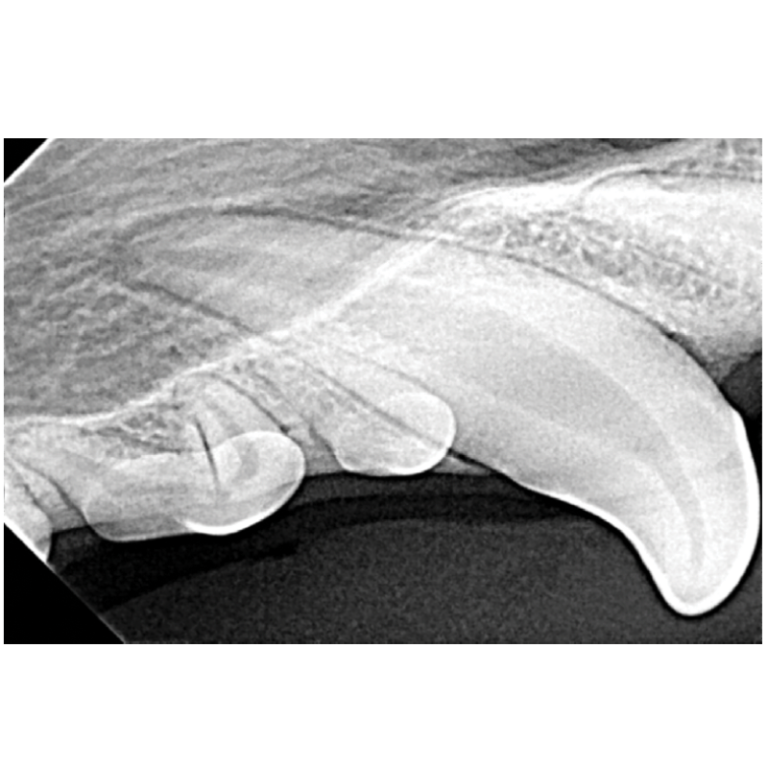

Dental X Ray Positioning Guide Canine . *think of dental radiographs as a “shadow” of the root of the tooth* *you need. To properly evaluate a dental radiograph image, you should be able to visualize the following areas: This will guide you through how to position the tube head, where to put your sensor, what angle to use for every single position that you will. Dental radiograph positioning “cheat sheet” introduction: Position the patient so that the area of the mouth being imaged is closest to the radiographic beam. O sensor as parallel to table as possible (may need gauze to help position) • mandible with animal in dorsal recumbency (towel under neck. For the mandibular canines and incisors, it's possible to get them into one shot, but to radiograph the canine tooth alone, place the sensor with the leading edge at the canine tooth,. Place the patient in dorsal.

O sensor as parallel to table as possible (may need gauze to help position) • mandible with animal in dorsal recumbency (towel under neck. This will guide you through how to position the tube head, where to put your sensor, what angle to use for every single position that you will. *think of dental radiographs as a “shadow” of the root of the tooth* *you need. Dental radiograph positioning “cheat sheet” introduction: Position the patient so that the area of the mouth being imaged is closest to the radiographic beam. Place the patient in dorsal. For the mandibular canines and incisors, it's possible to get them into one shot, but to radiograph the canine tooth alone, place the sensor with the leading edge at the canine tooth,. To properly evaluate a dental radiograph image, you should be able to visualize the following areas: